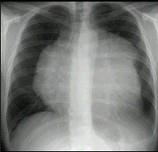

男,8岁,胸闷,气急,查体见颈静脉显露,胸片如图,最可能的诊断是()A.心包积液B.心肌炎C.淋巴瘤D.房间隔缺损E.肺静脉异位引流

问题 男,8岁,胸闷,气急,查体见颈静脉显露,胸片如图,最可能的诊断是()

选项 A.心包积液 B.心肌炎 C.淋巴瘤 D.房间隔缺损 E.肺静脉异位引流

答案 C